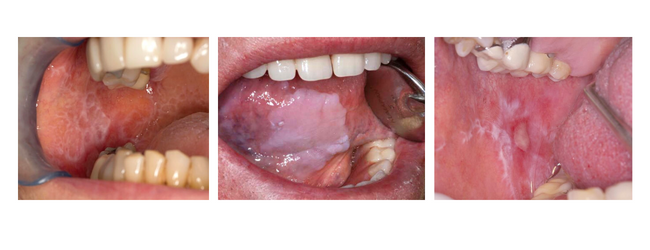

Cuando un paciente acude a la consulta por un problema a nivel dental o gingival, podemos pensar que el odontólogo se centrará en tratar dicha patología, sin tener en cuenta el resto de la boca. Pero esta no es la realidad en nuestra consulta. En Clínica Dental Urumea realizamos a todos nuestros pacientes una exploración oral detallada, teniendo en mente todas las estructuras que conforman la boca. Así, además de los dientes y la encía que los rodea, se exploran y valoran la lengua, el paladar, las zonas vestibulares, el suelo de boca, las zonas yugales, labios y zonas ganglionares. De esta forma tratamos de detectar cualquier lesión que pueda aparecer a nivel de los tejidos blandos bucales. Lesiones como el líquen plano, lesión liquenoide oral, leucoplasia, leucoplasia verrugosa, fibrosis oral submucosa, eritroplasia oral…lesiones todas ellas potencialmente cancerígenas. Lesiones orales bucales Nuestro trabajo como odontólogos es detectar precozmente la lesión tratando así de evitar su posible riesgo de malignización. En consecuencia, cuando se detecta alguna de estas lesiones en boca durante la exploración, se remite al paciente aun especialista en medicina oral. Dicho especialista realizará la biopsia de la zona, con dos claros objetivos; por una parte confirmar el diagnóstico clínico y por otra valorar la posible presencia de una displasia epitelial (proceso de cancerización). Esto nos permitirá realizar el tratamiento adecuado de la lesión existente, permitiendo la curación o la mejora del pronóstico de la gran mayoria de las lesiones orales.